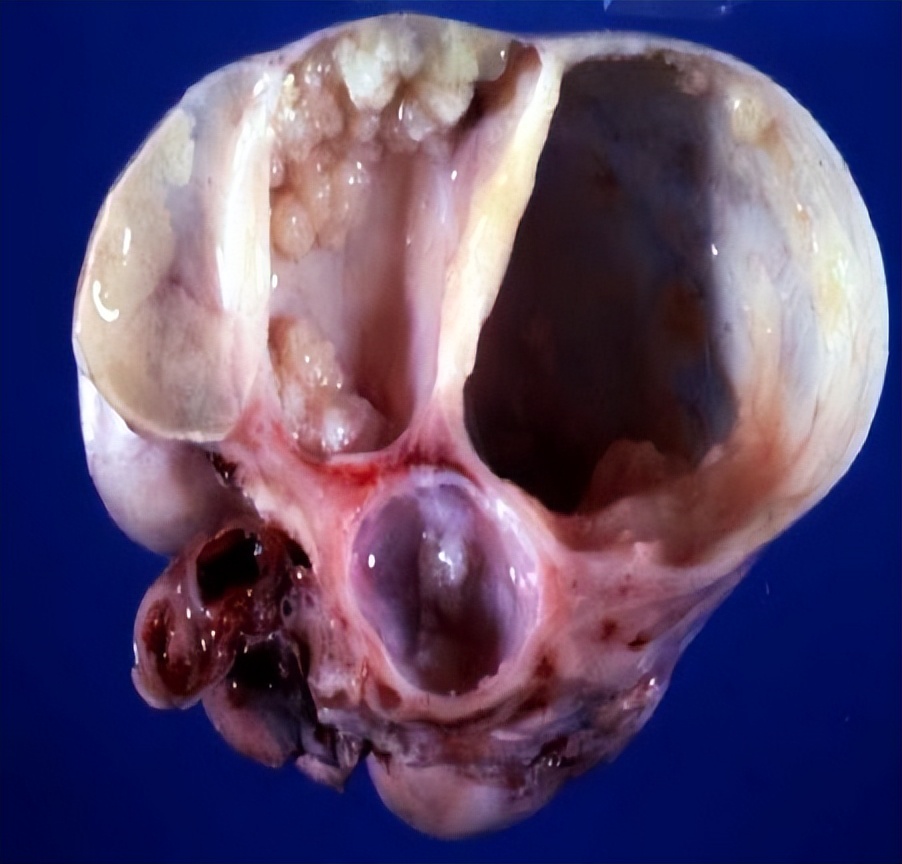

03、 卵巢畸胎瘤

这是一种病理性囊肿,好在一般是良性的。卵巢畸胎瘤由胚胎来源的细胞形成,可包含人体的各种成分,如头发、骨成分或脂质。

卵巢畸胎瘤的病因和发病机制至今不明,并且往往没有明显的临床症状。95%以上为良性的成熟性畸胎瘤,超声图像具有特征性,诊断比较明确,以手术切除为主。